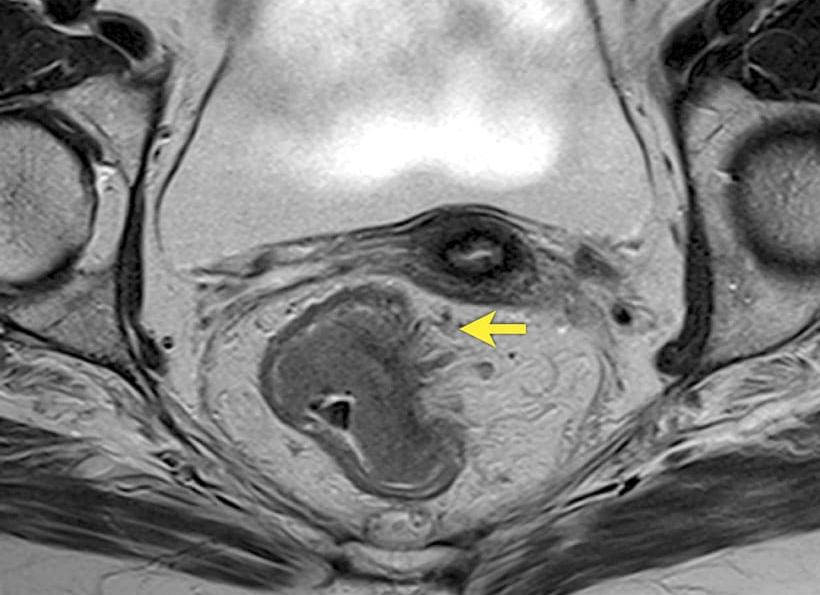

Особенно ценной является МРТ диагностика рака кишечника. Магнитно-резонансная томография при правильном строении кишечного тракта позволяет вычислить злокачественную опухоль на ранней стадии. На изображении злокачественные участки ткани окрашены в темный цвет. Согласно исследованиям, МРТ визуализирует даже стенозирующую опухоль, сквозь которую не проходит ультразвуковой датчик. Таким образом, методика позволяет своевременно вычислить аномальные явления и увеличивает шансы на полное выздоровление пациента. МР-томография является особенно результативной в исследовании рецидивирующих  раковых опухолей. Постоперационный контроль с применением УЗИ и КТ нередко приводит к ошибке: образовавшаяся новая опухоль воспринимается за рубец на месте удаления прежней опухоли. В отличие от альтернативных процедур исследования, МРТ получает четкие сигналы, которые абсолютно различают опухоль и рубцовую ткань.

Стоит отметить, что диагностированию рака на ранней стадии может помешать специфическое строение кишечника (петли наслоены друг на друга и закрывают некоторые участки). В таком случае рекомендуется к проведению колоноскопия или комплексное обследование, в котором применяются все возможные методы. В исследовании более поздних стадий, начиная со средней, магнитно-резонансная томография незаменима.